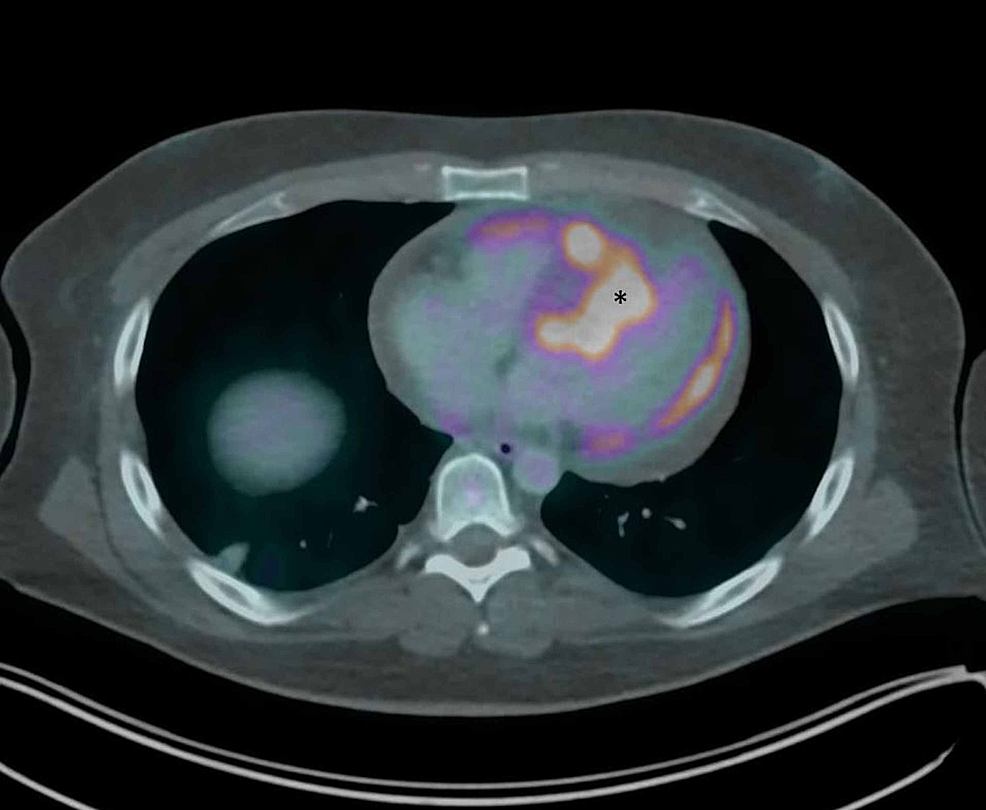

CT scan of the chest at the level of the heart. A tumor within the Heart Tumor X Ray Clinical features, such as patient age, location, and imaging characteristics of the mass will determine the likely differential diagnosis. Magnetic resonance imaging (mri) has proved to be very useful in the differential diagnosis between masses and neomasses,. In addition to radiologic evaluation of the mass itself, involvement of valvular apparatus, extent of. Multimodality imaging plays a pivotal role in diagnosis. Heart Tumor X Ray.

Cureus A Silent Left Atrial Myxoma A Rare Benign Cardiac Tumor Heart Tumor X Ray Tumors encompass a broad set of. They can be either benign (noncancerous) or. Cardiac myxoma is the most common primary cardiac tumor, usually found in the left atrium, and can cause various symptoms. Metastases and pseudotumors (eg, thrombus) are much more common. This article provides an overview of cardiac masses and reviews the optimal mr imaging techniques for their assessment.. Heart Tumor X Ray.

An unusual presentation of a giant pleural tumor ejournal.gr Heart Tumor X Ray Multimodality imaging plays a pivotal role in diagnosis and surgical planning of cardiac masses. This article provides an overview of cardiac masses and reviews the optimal mr imaging techniques for their assessment. Cardiac tumors (also called heart tumors) are growths that form in your heart. In addition to radiologic evaluation of the mass itself, involvement of valvular apparatus, extent of.. Heart Tumor X Ray.